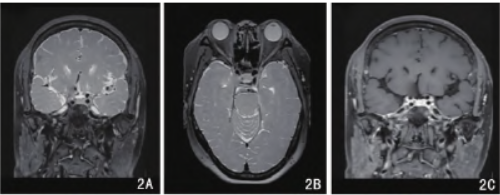

后患者行磁共振颅内动脉高分辨血管壁成像平扫+增强显示垂体右前份见一大小约为2mm×2mm×2mm的结节,呈等T1短T2信号灶,增强后可见强化减低,强化程度明显低于垂体实质。垂体上缘平坦,垂体柄居中,视交叉显示清晰(图2)。

2a.png

2b.png

图2患者术前磁共振冠状位及水平位血管高分辨成像显示,垂体右前T2WI低信号微小结节(A、B);增强后强化减低,强化程度低于垂体实质(C、D)